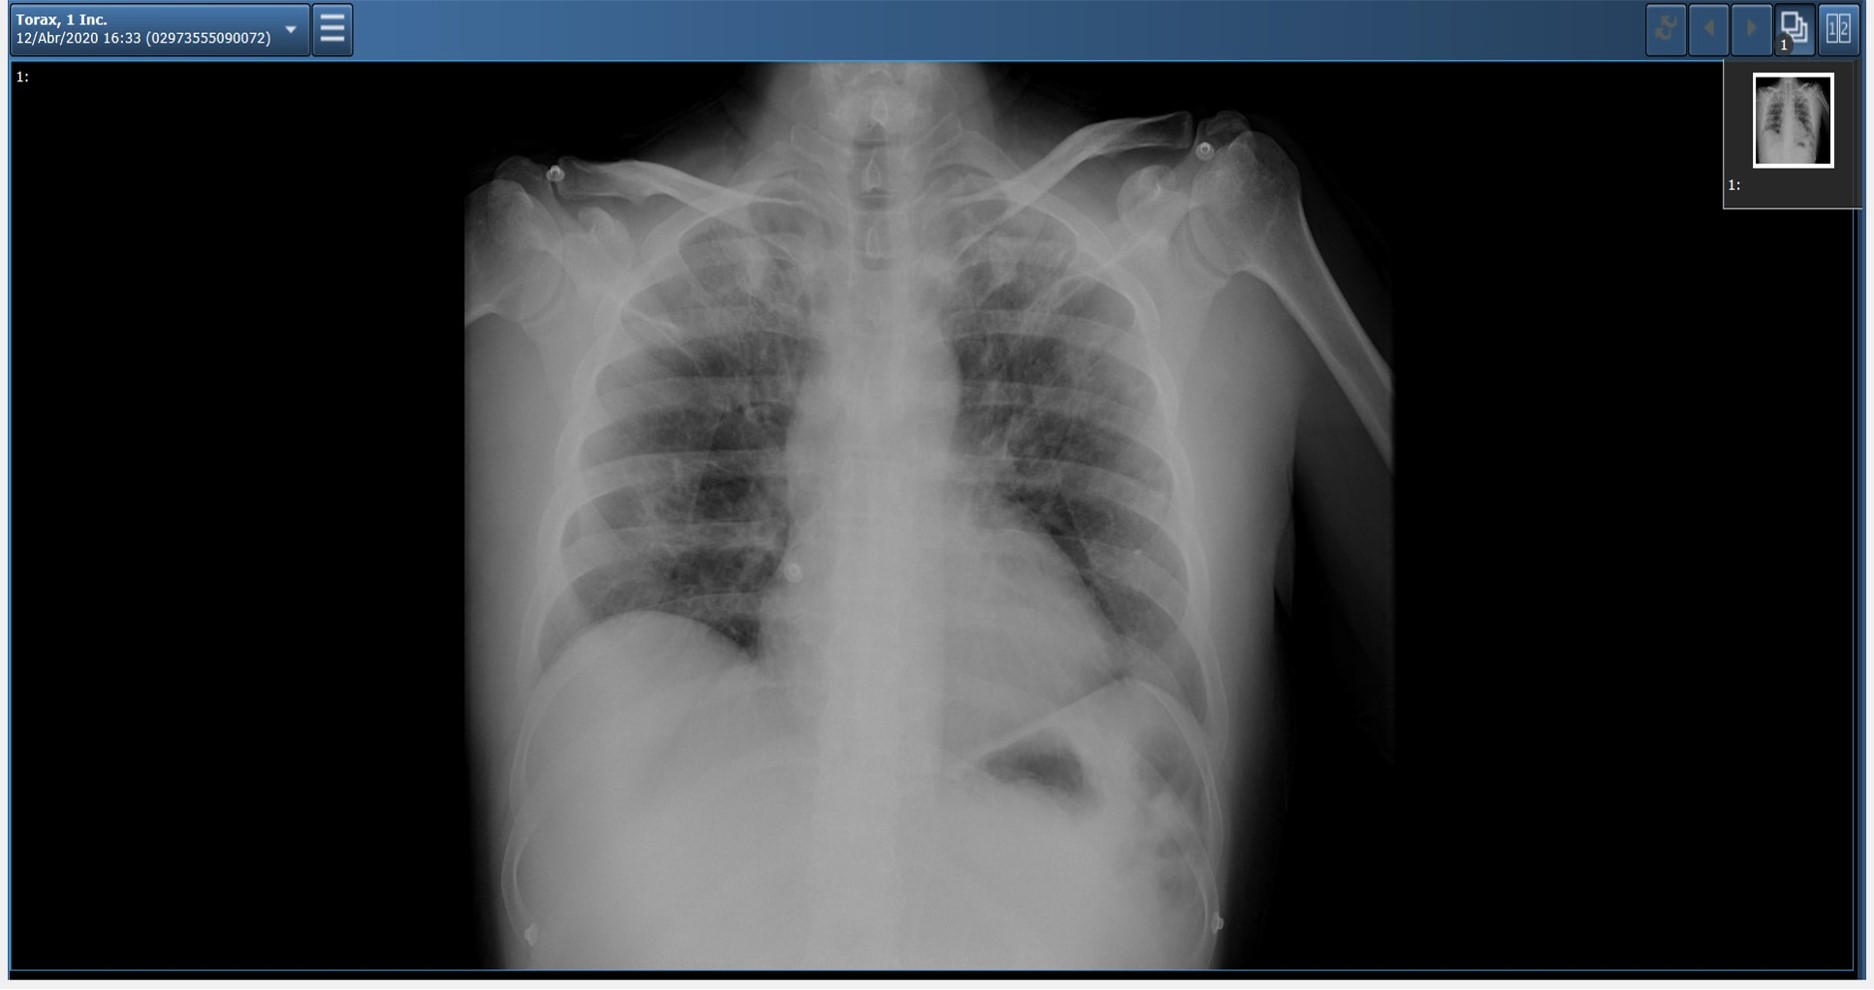

Radiografia do primeiro farmacêutico que contraiu COVID-19

Tanto significado tem o frasquinho da primeira vacina administrada a um português como a radiografia do primeiro farmacêutico que entre nós contraiu a COVID-19, ou o primeiro cartune de Vasco Gargalo sobre o tema. Tão válido é um exemplar do ventilador «made in Portugal» como a máscara confeccionada por uma vizinha do jornalista Bento Rodrigues, que fez questão de a apresentar na SIC. A capa do Diário de Notícias, aludindo ao primeiro caso em Portugal, detectado no Hospital de São João, no Porto, ou a amostra que lhe diz respeito.